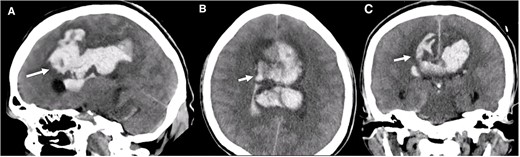

A multislice computed tomography (CT) without contrast revealed an extensive interhemispheric hematoma in the frontoparietal region, subarachnoid hemorrhage, and intraventricular hemorrhage in the adjacent area (Fisher grading score of IV) (Fig. 1). In addition, cerebral angiotomography and 3D reconstruction imaging suggested the presence of two abnormal vascular lesions: (i) a fusiform aneurysm of 12 × 7 mm in an accessory A2 portion of the ACA and (ii) an unruptured saccular aneurysm of 3.3 × 2.8 mm in the distal segment of the basilar artery adjacent to the anterolateral surface of the P1 segment and the left superior cerebellar artery (Figs 2 and 3).

Three-dimensional reconstruction imaging. (A) Superior view of the Circle of Willis shows a variant of the ACA with an accessory A2 branch (white arrow) and a saccular aneurysm of 3.3 × 2.8 mm at the basilar artery (yellow arrow). (B) Inferior–superior view depicts the configuration of the ACA with a triplicated A2 segment and a fusiform aneurysm of 12 × 7 mm emerging in its distal portion, with branches arising from the aneurysm sac (white arrow). (C) Superior view of the anterior and posterior circulation exhibits the complex anatomy of the A1 and A2 segments (green arrows), the accessory A2 segment and distal fusiform aneurysm (white arrows), and the basilar aneurysm (yellow arrow). (D) Lateral view shows the course of the triplicated A2 segment with the fusiform aneurysm arising distally (white arrow) and the small basilar aneurysm (yellow arrow).